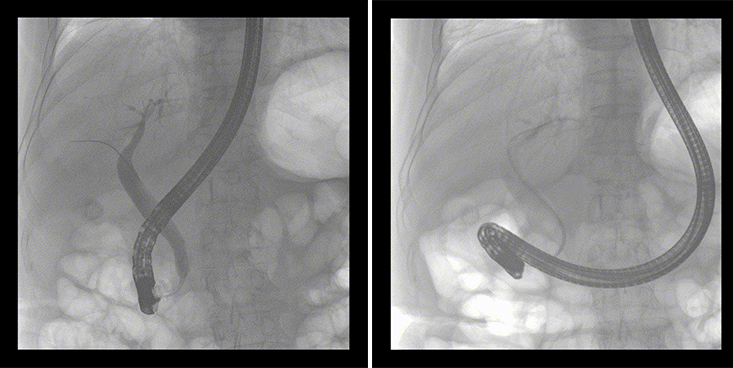

ERCP(经十二指肠镜下逆行胰胆管造影)现已成为比较成熟的微创介入技术,被广泛的应用于临床,ERCP也是消化内镜领域难度大、风险大、技术复杂的微创手术,其并发症多为致命性,ERCP手术对医生的要求很高,因此,ERCP医生又被称为“刀尖上的舞者”。因为手术难度较大,过程复杂,需要C形臂精准的配合,对影像清晰度的要求也非常高。

移动式平板中C为本次ERCP手术提供实时无损高清影像,帮助医生精准定位。“成像效果非常棒!完全不输国际大牌的医学影像设备……”鼓楼医院江北国际医院内镜中心手术团队对糖心vlog 移动式平板中C的成像效果给与了高度的评价。

移动式平板中C术中影像